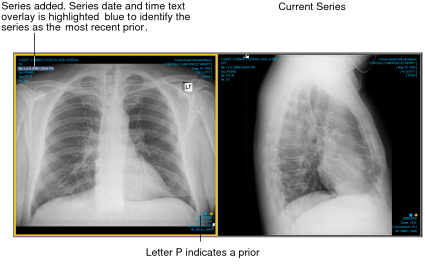

When you open a new study or series for comparison, the differences in study or series date and time or patient name are highlighted in the text overlay so that you can distinguish them. If the accession number in the new study or series differs from the original, the study/series date and time or study/series date and study/series time text overlays are highlighted by using the multiple-prior color coding scheme. If the patient ID in the new study or series differs from the original, a gray filled rectangle appears behind the study/series date and time or study/series date and study/series time and patient name text overlays.

For example, if you open a series in a prior study for the same patient and the series date and time text overlay is highlighted blue, this identifies the series as the most recent prior making it easier to differentiate. If you then add a series from another patient, a gray filled rectangle appears behind the name and the series date and time text overlays on the new series, as this information does not match that of the original. In addition to the text overlay highlight color, the letter P appears at the bottom of a prior.

In the case of a prior MR study, the acquisition date and time text overlays can also appear highlighted.